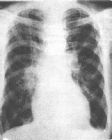

典型的ARDS臨床經過可分為4期:第一期,又稱急性損傷期,為潛伏期,主要為原發病的臨床表現;第二期,又稱穩定期,在發病24~48h以後,呼吸頻率增快,肺部可聞及濕性囉音,Pao2下降;第三期,急性呼吸衰竭期,病情發展迅速。呼吸困難加重,呼吸窘迫。PaO2進行性下降,給氧難以糾正,胸片出現典型的瀰漫性霧狀浸潤陰影;第四期,嚴重缺氧和二氧化碳瀦留,最後導致心衰、休克、昏迷、嚴重低氧導致死亡。

3.早期ARDS的診斷應具備6項中3項。⑴呼吸頻率>28次/分。⑵(FiO20.21)PaO2≤7.90kPa(60mmHg)>6.60kPa(50mmHg)⑶PaCO2<4.65kPa(35mmHg)⑷PaO2/FiO2≤39.90kPa(≤300mmHg)>26.60kPa(>200mmHg)⑸(FiO21.0)PA-aO2>13.30kPa(>100mmHg)<26.60kPa(<200mmHg)⑹胸片示肺泡無實變或實變≤1/2肺野。

4.晚期ARDS的診斷應具備下述6項中3項:⑴呼吸窘迫,頻率>28次/分。⑵(FiO20.21)PaO2≤6.60kPa(≤50mmHg)⑶PaCO2>5.98kPa(>45mmHg)⑷PaO2/FiO2≤26.6kPa(≤200mmHg)⑸(FiO21.0)PA-aO2>26.6kPa(>200mmHg)⑹胸片示肺泡實變≥1/2肺野。

4、胸部X線檢查顯示兩肺浸潤陰影。